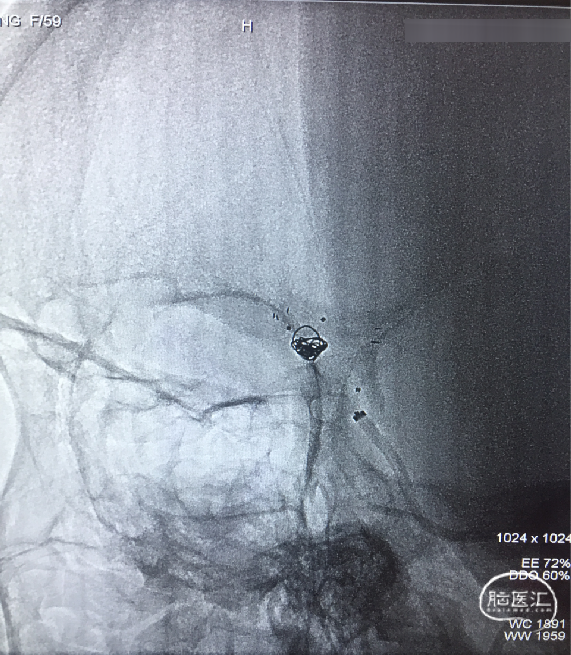

支架内球囊扩张

Synchro(200cm)携Echelon-10到达RACA A3(左图)。Synchro(300cm)交换Gateway1.5×9mm及Ultra-soft SV 2.0×20mm支架内扩张(6 atm)(右图)。

术后影像

扩张术后造影:显示RACA血流恢复。

术后30分钟造影:LICA正侧位显示良好。

术后支架重建及蒙片:显示支架完全打开,贴壁充分,动脉瘤栓塞致密。